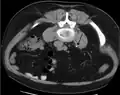

Otherwise a noncontrast helical CT scan with 5 millimeters (0.2 in) sections is the diagnostic method to use to detect kidney stones and confirm the diagnosis of kidney stone disease.[16][57][61][66][7] Near all stones are detectable on CT scans with the exception of those composed of certain drug residues in the urine,[59] such as from indinavir.

Where a CT scan is unavailable, an intravenous pyelogram may be performed to help confirm the diagnosis of urolithiasis. This involves intravenous injection of a contrast agent followed by a KUB film. Uroliths present in the kidneys, ureters, or bladder may be better defined by the use of this contrast agent. Stones can also be detected by a retrograde pyelogram, where a similar contrast agent is injected directly into the distal ostium of the ureter (where the ureter terminates as it enters the bladder).[61]